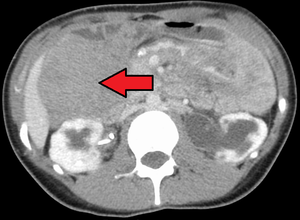

ورم رباطي كما هو موضح في الاشعة المقطعية | |

الورم الليفي العدواني هو حالة نادرة تتميز بوجود أورام خبيثة . تنشأ الأورام الخبيثة من خلايا تسمى الخلايا الليفية ، والتي توجد في جميع أنحاء الجسم وتوفر الدعم الهيكلي والحماية للأعضاء الحيوية ، وتلعب دورًا مهمًا في التئام الجروح. تميل هذه الأورام إلى الحدوث عند النساء في الثلاثينيات من العمر ، ولكن يمكن أن تحدث لأي شخص في أي عمر. يمكن أن تكون إما بطيئة النمو أو خبيثة. ومع ذلك ، فإن الورم الليفي العدواني عدواني محليًا ويمكن أن يسبب مشاكل تهدد الحياة أو حتى الموت عندما يضغط على الأعضاء الحيوية مثل الأمعاء والكلى والرئتين والأوعية الدموية والأعصاب. معظم الحالات متفرقة ، لكن بعضها يرتبط بداء السلائل الغدي العائلي (FAP). ما يقرب من 10 ٪ من الأفراد الذين يعانون من متلازمة جاردنر ، وهو نوع من FAP مع ميزات خارج القولون ، لديهم أورام رباطية .[1]